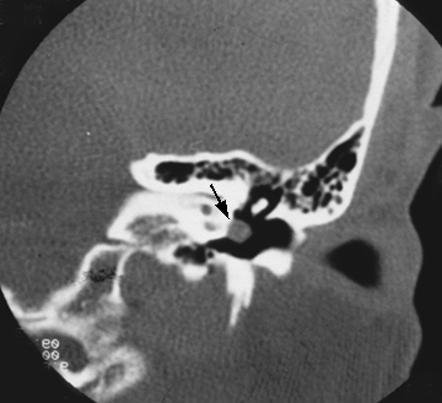

occipital condyle fracture